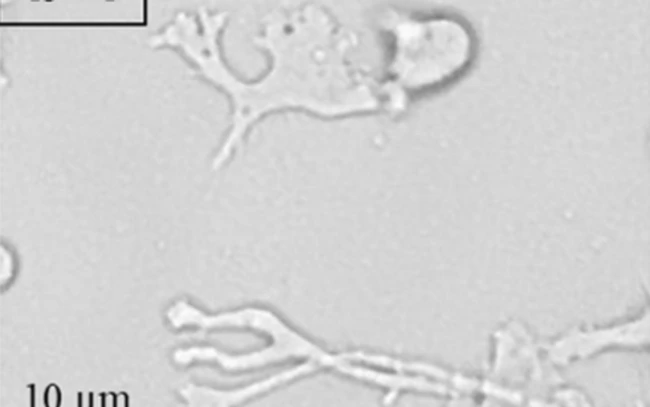

FOTO Wikipedia commons

Un întreg ţinut din statul american Florida a fost pus sub alertă după ce un localnic a luat o amibă care se hrăneşte cu creierul uman, potrivit BBC. Organismul unicelular provoacă o variantă foarte rară de encefalită care progresează foarte rapid şi omoară persoana infectată într-o săptămână.

Amiba trăieşte în apă dulce şi devine activă la căldură. Ea intră în corp prin nas şi atacă direct creierul. Riscul cel mai mare de infectare este în lunile iulie, august şi septembrie.